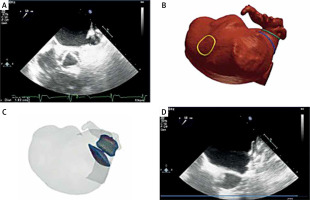

Case 3

A 79-year-old woman with paroxysmal atrial fibrillation (CHA2DS2-VASc 4, HAS-BLED 3 points) was admitted to our hospital for LAA closure due to recurrent bleeding from the gastrointestinal tract of unknown cause. Preprocedural echocardiography was very demanding because of the anatomy of the appendage. Measurements of the right device size by TEE were not possible to perform adequately due to very difficult visualization. CT was performed and revealed chicken wing anatomy of the LAA and excluded presence of thrombus (Figure 2). The case was assessed with FEops and an Amulet 22 mm was finally used after personal analysis. No complications occurred and the device was stable with good sealing in the follow-up. In this patient measurements by FEops were crucial for our team.